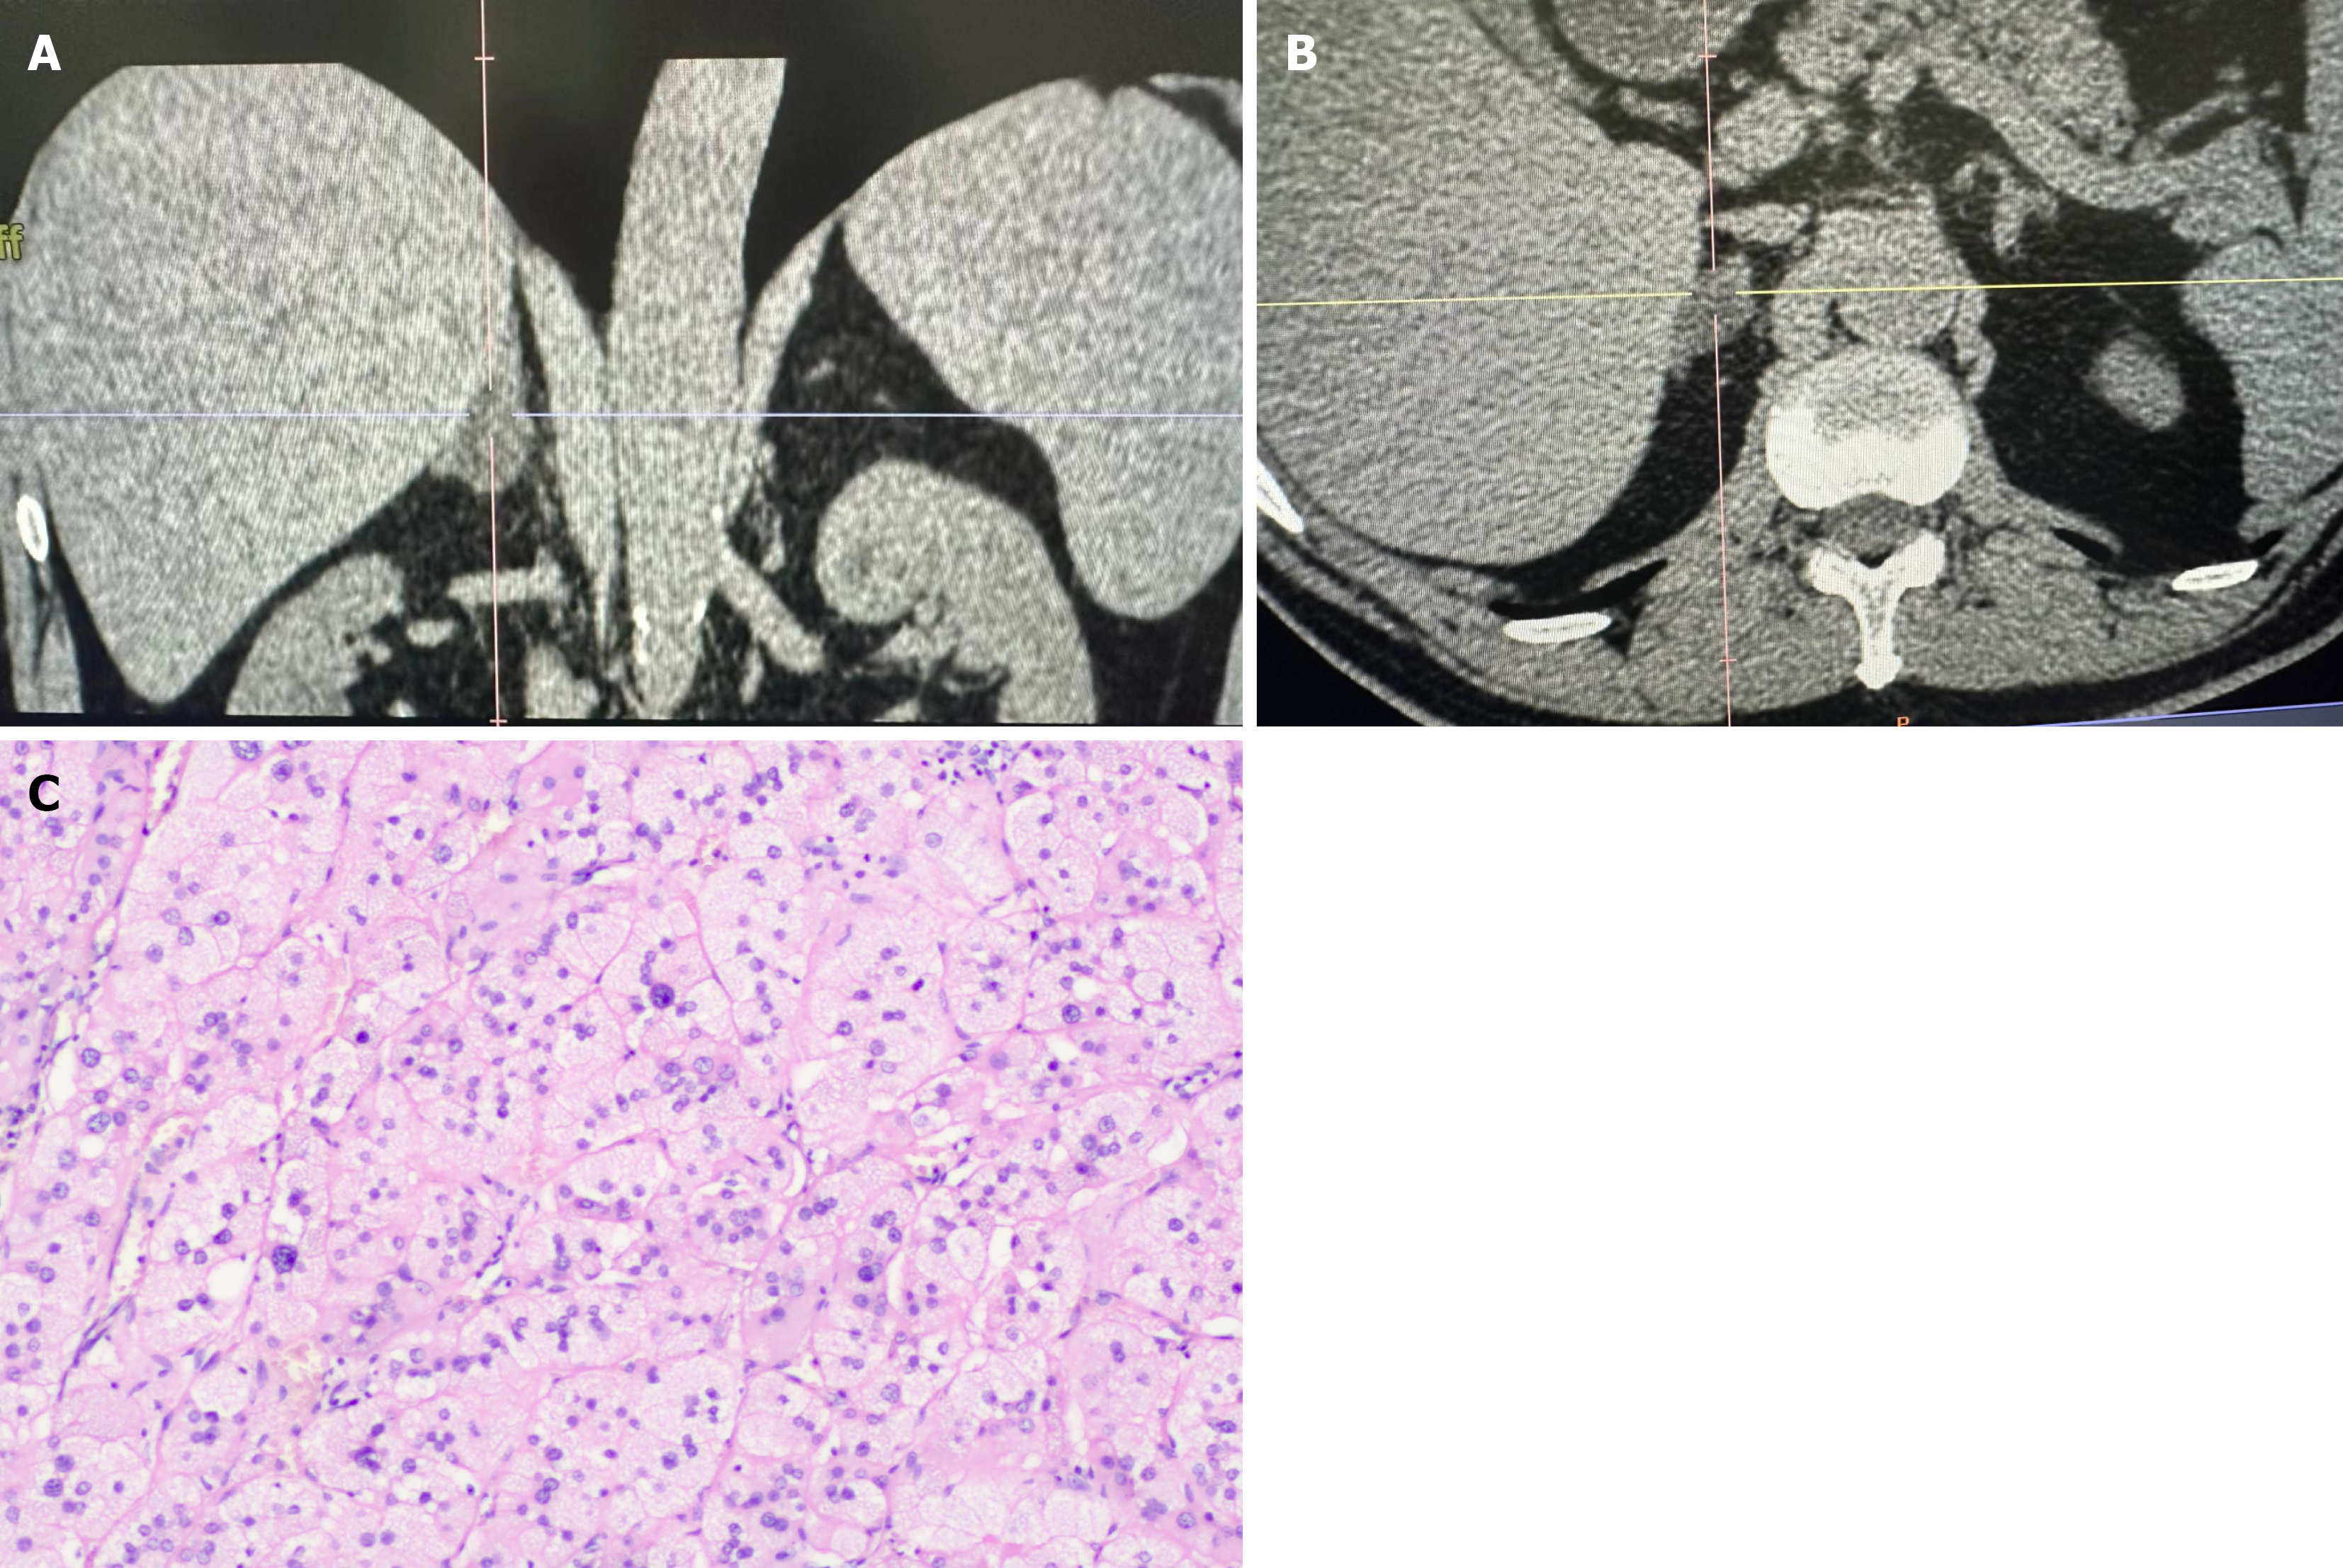

Thyroid ultrasound: A hypoechoic nodule with unclear margins and an irregular shape was observed on the deep surface of the right thyroid lobe. The nodule showed punctate echogenic foci with a longitudinal-to-transverse ratio > 1. Several mixed echogenic nodules were identified in the right lobe, the largest measuring approximately 0.6 cm × 0.4 cm × 0.3 cm, with clear borders and a regular shape. A mixed echogenic nodule was also found in the left lobe, measuring approximately 0.7 cm × 0.6 cm × 0.5 cm, with clear borders and a regular shape. A mixed echogenic mass measuring approximately 6.4 cm × 4.5 cm × 5.3 cm was found in the left neck, with clear borders and regular shape. Color Doppler flow imaging revealed blood flow signals within the mass. The mass was located anterior to the left common carotid artery and posterior to the internal jugular vein, with compression of the jugular vein and almost no visible lumen (Figure 1). There was blood flow stagnation in the upper portion of the mass, with spontaneous imaging visible.

Neck and chest CT scan with contrast: A slightly low-density mass was observed adjacent to the left thyroid lobe, with an unclear boundary between the mass and the upper portion of the thyroid. The largest section measured approximately 4.0 cm × 5.5 cm. On the contrast-enhanced scan, the mass exhibited uneven enhancement (Figure 2).

The lesion extended into the lower chest cavity, with the left common carotid artery lying deep into the mass. The mass was closely adherent to the left common carotid artery, and the boundary between the mass and the left internal jugular vein was unclear. The left internal jugular vein was almost invisible due to compression, and collateral venous circulation was visible around the mass. The neighboring trachea showed slight compression but no significant narrowing.

The right thyroid showed a PTC (follicular subtype) with a single focus. The tumor measured 0.8 cm × 0.6 cm × 0.6 cm, with capsule invasion, but no nerve or vascular invasion was observed. The remaining thyroid tissue showed no significant pathological changes. Immunohistochemistry results were CK19 (+), CD56 (-), and TPO (-). In the left thyroid, follicular nodular changes were noted. No cancer metastasis was detected in any of the 26 Lymph nodes examined (Figure 5).

Specifically, the left side lymph nodes in groups II (0/10), III (0/6), IV (0/5), central group (0/4), and group Vb (0/1) showed no signs of malignancy. The right central group lymph nodes contained only minimal fibrofatty tissue. The left neck mass was diagnosed as PTC (classic type), with a single focus and a tumor size of 6 cm × 5 cm × 4 cm. The tumor showed necrosis that invaded the capsule, with evidence of nerve invasion. Immunohistochemistry results were TTF-1 (+), Tg (+), CK19 (+), MC (+), Galectin-3 (+), CyclinD1 (+), Ki67 (+, approximately 8%), CD31 (vascular +), and D2-40 (lymphatic +) (Figure 6).